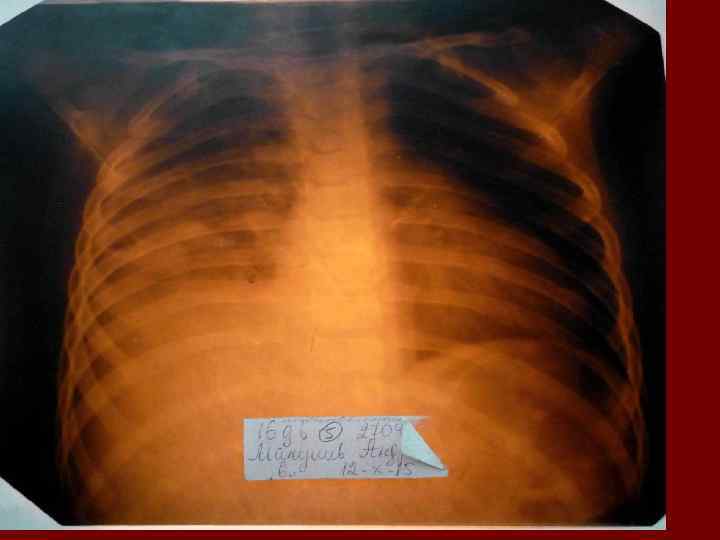

Долевая пневмония характеризуется лобарным пневмоническим инфильтратом. Крупозная ( пневмококковая) пневмония диагностируется прежде всего по клиническим данным. Крупозная пневмония сохраняет свою типичную картину пневмококковой пневмонии: острое начало с характерными клиническими данными, циклическое течение, несклонность к деструкции, гомогенной и лобарной инфильтративной тенью при рентгенологическом исследовании. Вместе с тем, широкое использование антибиотиков способствовало значительному снижению числа крупозных пневмоний у детей. Интерстициальная – редкая форма пневмоний, при которой оказывается поражен прежде всего интерстиций. Как правило, интерстициальная пневмония обусловлена вирусами, пневмоцистами, внутриклеточными микроорганизмами и грибами.

Морфологическую форму пневмонии определяют по клинико – рентгенологическим данным: выделяют очаговую, очагово – сливную, долевую ( крупозную), сегментарную и интерстициальную пневмонии. Очаговая – наиболее распространенная форма. Пневмонические очаги чаще бывают размером 1 см и более. Очагово – сливная – инфильтративные изменения в нескольких сегментах или во всей доле легкого, на фоне которых могут быть видны более плотные участки инфильтрации и/или полости деструкции. Сегментарная – в процесс вовлекается весь сегмент, который, как правило, находится в состоянии гиповентиляции, ателектаза. Морфологическая картина воспаления при очаговых и сегментарных пневмониях связана с первичным инфекционным воспалением в бронхах, что дает основание отнести эти варианты поражения легочной ткани к бронхопневмониям, нередко сопровождающихся бронхообструктивным или бронхообтурационным синдромами. В настоящее время данный тип пневмоний у детей встречается наиболее часто.